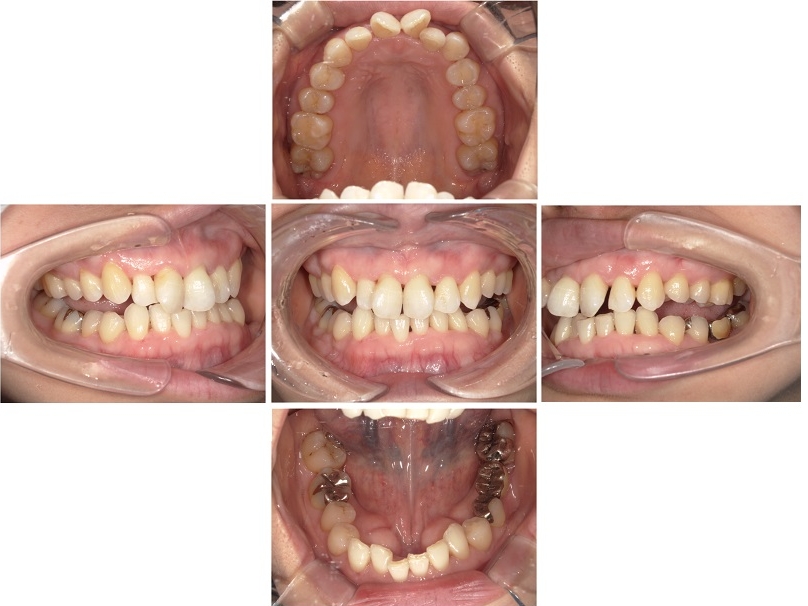

しかし今回は、歯周内科治療によって十分な改善が確認できたため、外科処置は行わず左下のブリッジ治療へと進むことができました。

歯周内科治療から左下ブリッジの治療まで、全体の治療期間は約6ヶ月で終了しています。

画像をクリックすると拡大・詳細コメントを確認いただけます